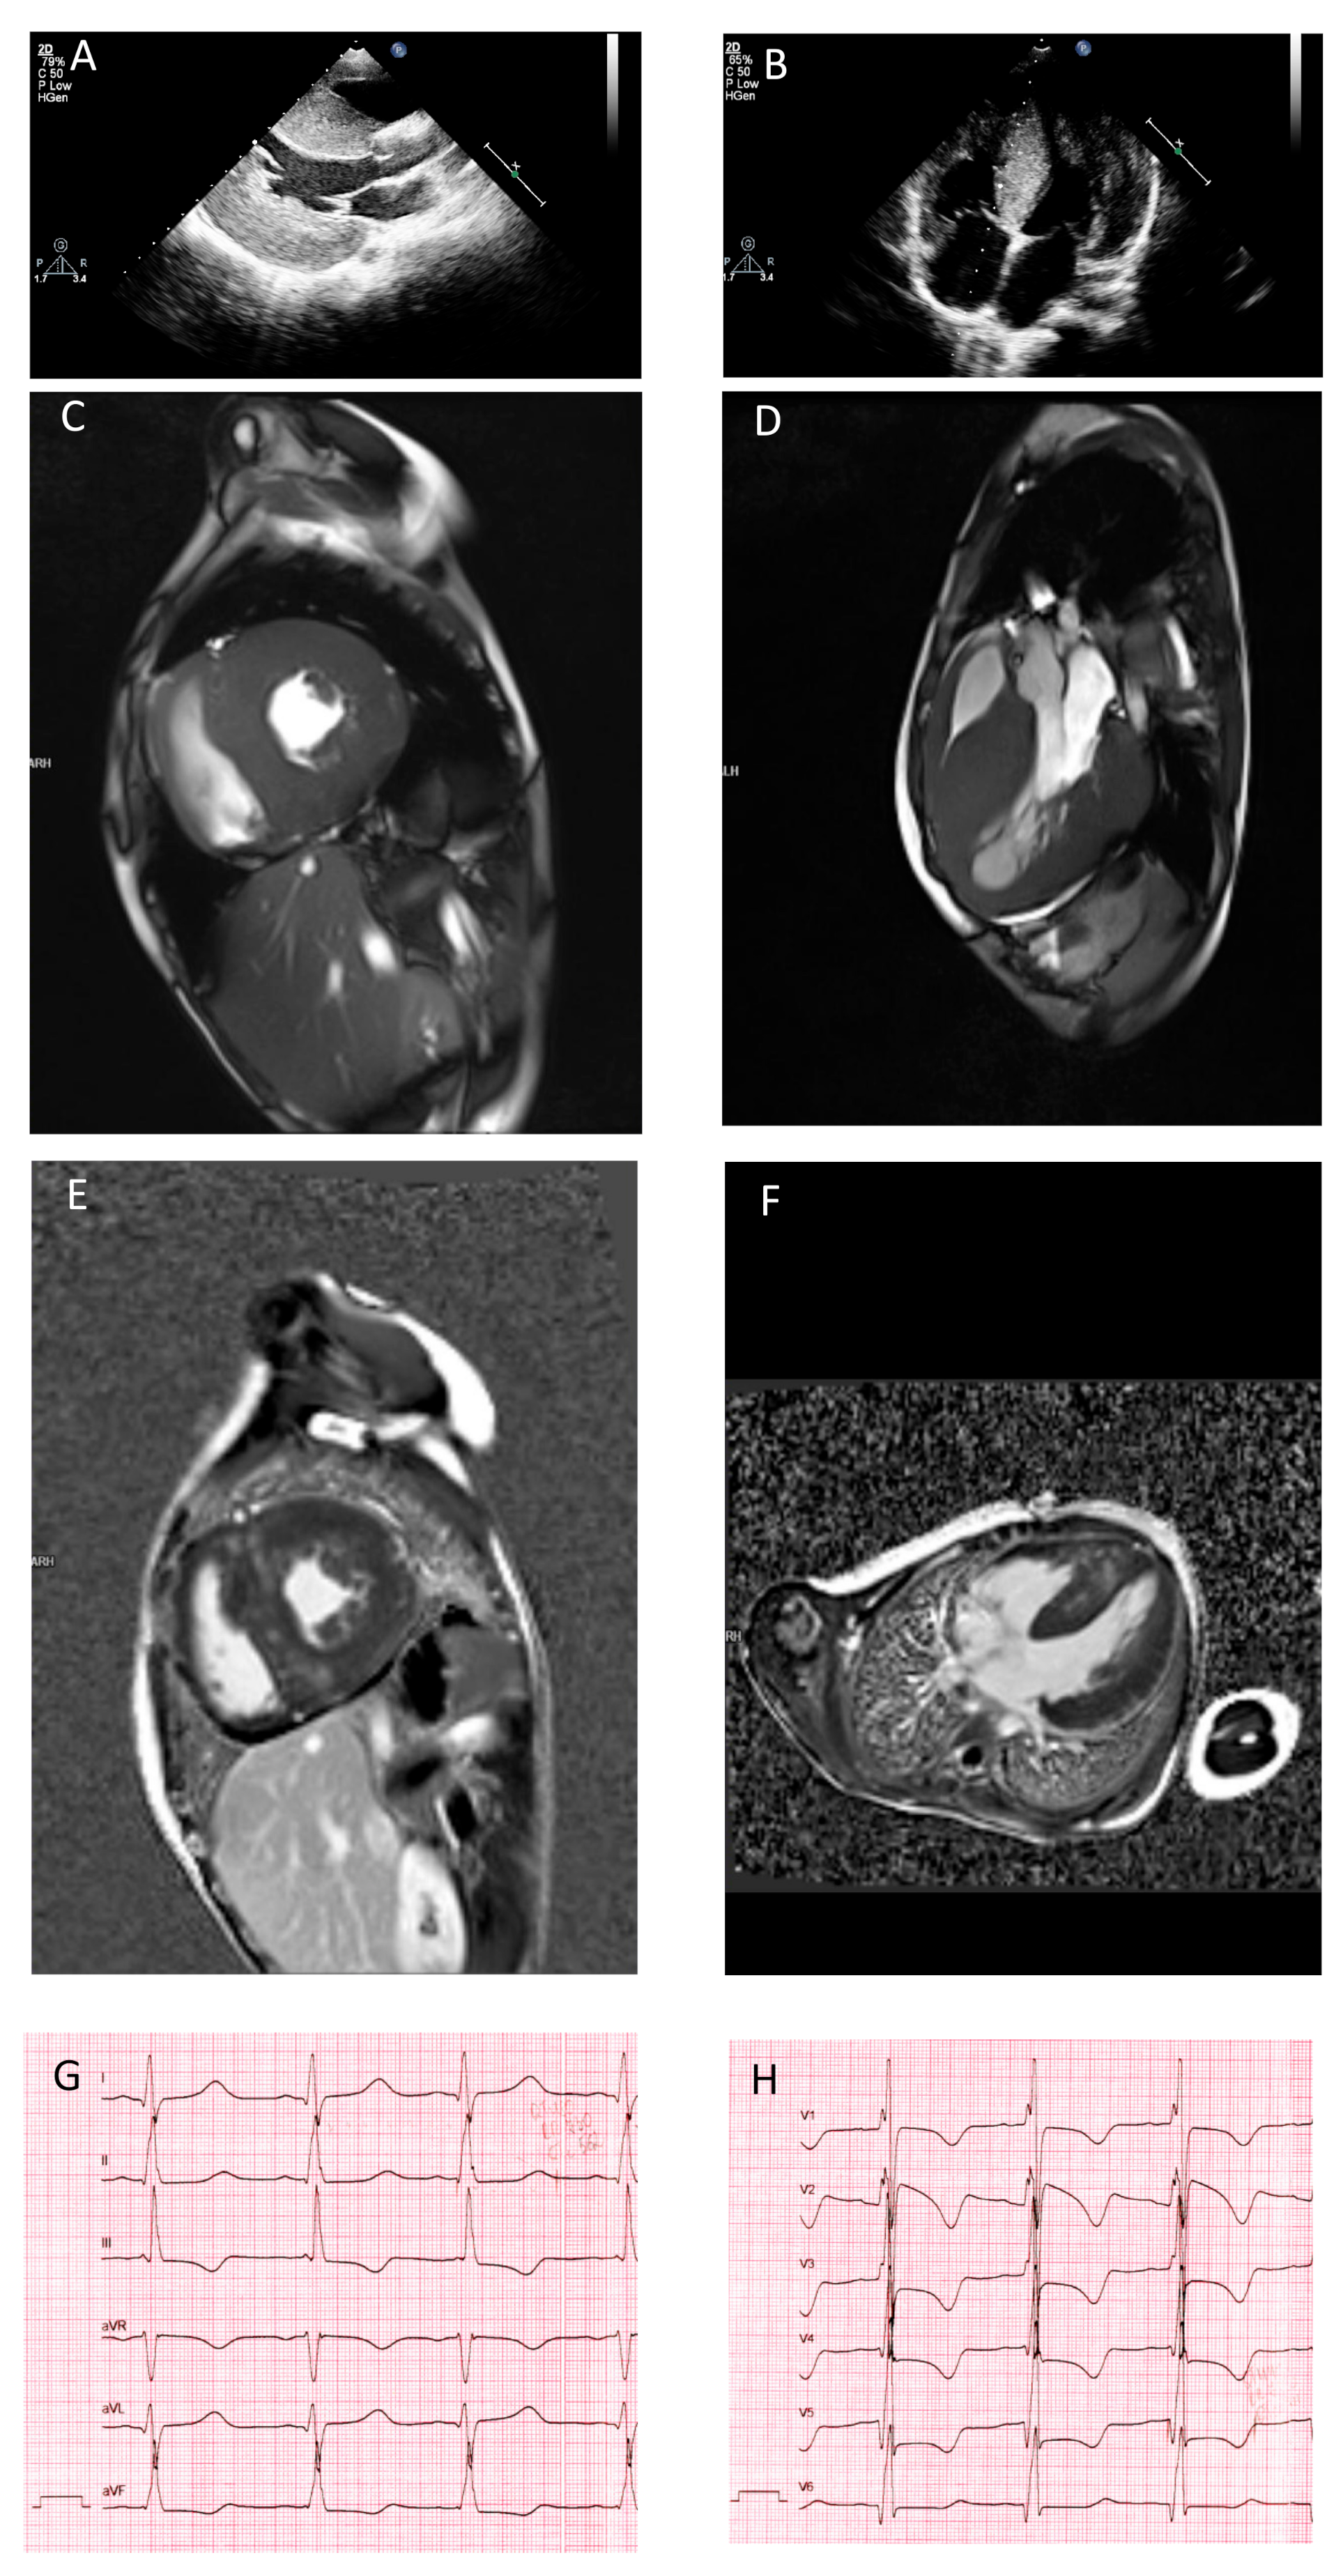

3.1. Clinical Presentation